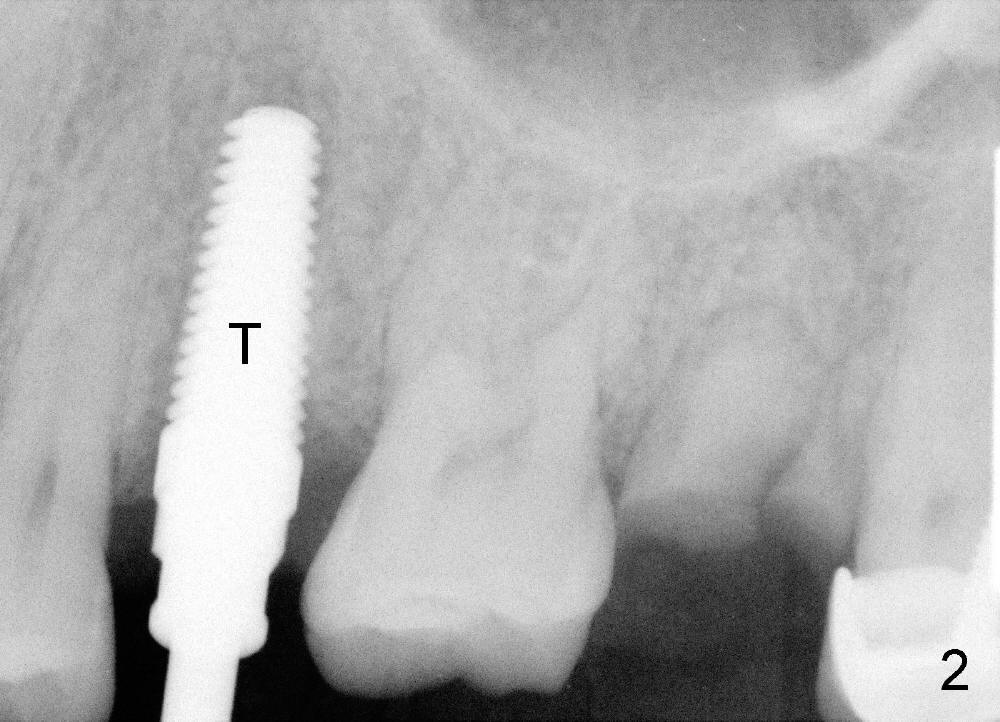

牙根拔除后,牙槽窝深度十六毫米(从牙龈缘算起),开始钻洞十七毫米深,一直用到钻头直径四点五毫米,然后用适当力量旋入五乘十七毫米tap(图二),后者与牙槽窝接触很紧,突然意识到即刻植牙后,牙龈会有所退缩,所以钻洞再深一毫米,最后旋入五乘十七毫米植牙(图三I),torque超过六十Ncm。原先第一双尖牙(图一黄线)比第二长些,术后植牙稍微比第一双尖牙长(图三箭头),总之在新骨头里钻洞不需要太多,在这个病例里,大约二个毫米。